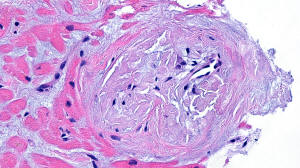

Figure C. Trichrome stain x20

Histology: A heart biopsy was performed and H&E sections (Figures A & B) show myocardial tissue with unremarkable cardiomyocytes and mild to moderate interstitial fibrosis, confirmed by trichrome staining (Figures C and D). The small vessels show moderate wall thickening with accumulation of smudgy, light eosinophilic material with cracking appearance, which stains light purple with the trichrome staining. Congo red staining (Figure E) viewed under polarized light shows apple-green birefringence consistent with amyloid deposits. Electron microscopic examination (Figures F and G) reveal cardiomyocytes and vascular structures surrounded by a fibrillary material (Figure G) consistent in size and appearance with amyloid (n 5-15 nanometer).